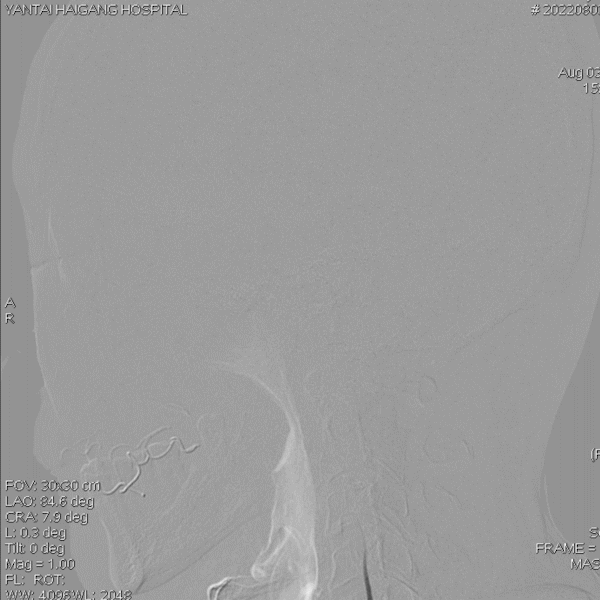

病变情况分析:右桡动脉穿刺,置6F桡动脉鞘管,5F多功能导管在泥鳅导丝辅助下脑血管造影提示:右椎动脉V4段重度狭窄(约90%)。

导丝怎么扩【载药时代 球扩天下】NOVA DES®颅内药物洗脱支架在椎动脉颅内段重度狭窄的应用二例_https://www.jmylbn.com_新闻资讯_第31张

导丝怎么扩【载药时代 球扩天下】NOVA DES®颅内药物洗脱支架在椎动脉颅内段重度狭窄的应用二例_https://www.jmylbn.com_新闻资讯_第32张

泥鳅导丝携5F 115cm颅内支撑导管,至右椎动脉V2段。

在颅内支撑导管支撑下,将0.014'' 300cm微导丝,通过狭窄节段将其放置在基底动脉中段。将2.0mm*10mm球囊打起预扩狭窄部位,然后更换赛诺神畅 颅内药物洗脱支架NOVA DES® 2.5*10mm延微导丝顺利通过狭窄节段,再次造影见定位准确,缓慢扩张球囊释放支架。